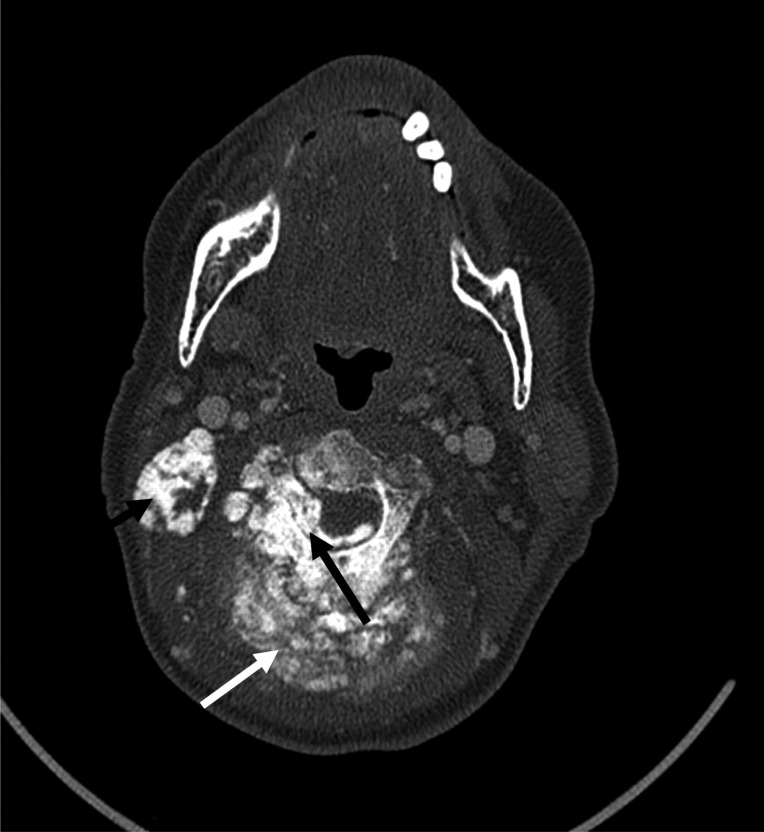

我们报告一个非常罕见的病例高级别骨肉瘤的颈椎在62岁的妇女。她表现出相对较短的后颈部肿胀和颈部淋巴结病病史。这与最初的声音嘶哑、体重明显减轻和右上臂神经根症状相关,并发展为截瘫。根据颈部的MR和CT成像以及右侧锁骨上肿大淋巴结的切除活检,组织学显示为颈椎高级别原发性骨肉瘤。

We report a very rare case of a high grade osteosarcoma of the cervical spine in a 62-year-old woman. She presented with a relatively short history of a swelling in the posterior neck and cervical lymphadenopathy. This was associated with hoarseness of the voice, significant weight loss, and right upper arm radicular symptoms initially, progressing to paraplegia. Based on MR and CT imaging of the neck and an excision biopsy of an enlarged right supraclavicular lymph node, the histology revealed a high grade primary osteosarcoma of the cervical spine.